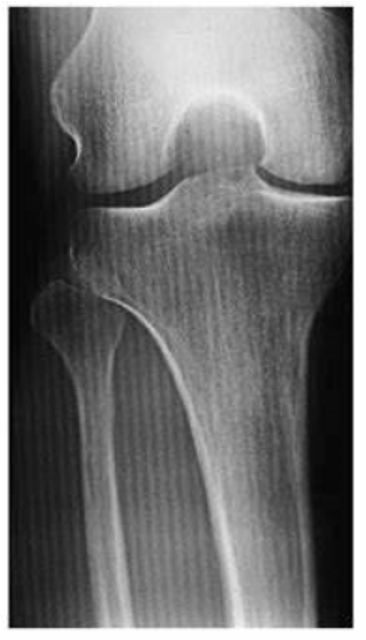

Patient Thickness

Imaging thick parts of the body results in more scatter radiation

With increasing patient thickness, more x-rays undergo multiple scattering

Types of tissue (muscle, fat, bone) and pathology play a role in production of scatter